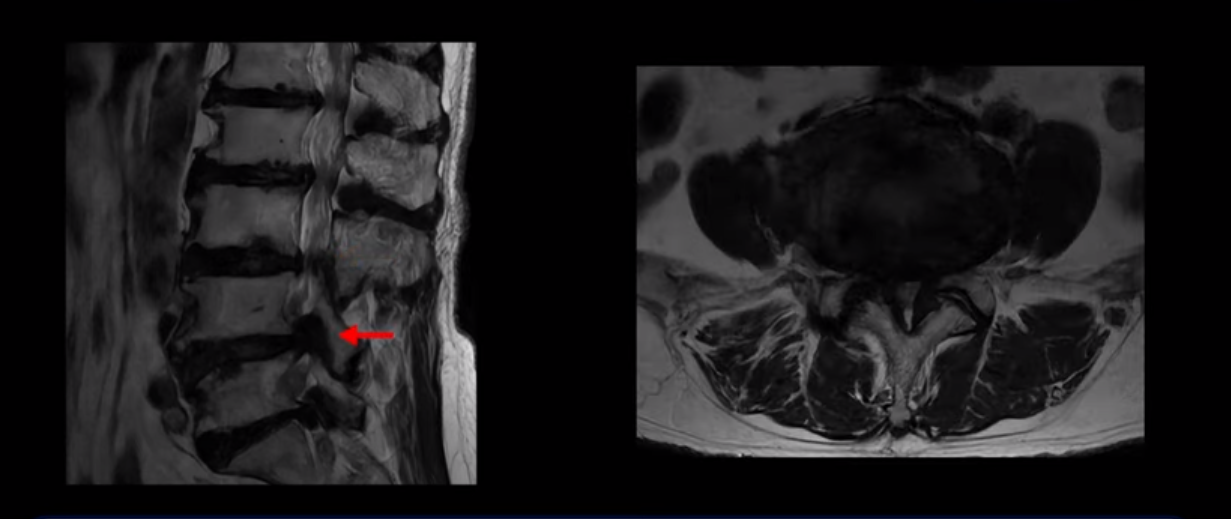

이 환자분은 MRI로 보면 허리 여러 마디가 신경이 매우 심하게 눌려 보이는 분입니다. 이분 MRI를 보면서 간단히 설명해 드린 후 어떻게 이렇게 신경이 심하게 눌린 환자분이 수술 없이 근육신경재활치료로 좋아질 수 있는지, 다리가 아파 걷지 못하는 환자가 어떻게 안 아프고 잘 걸을 수 있게 되는지, 10년 동안 괴로웠던 양 발의 시린 증상은 어떻게 사라질 수 있는지, 치료는 어떻게 하는지 자세히 설명 드리겠습니다.

MRI 보시면 (2-8) 허리의 5마디가 전부 다 심하게 퇴행되어 있습니다.

5마디 전부 다 심한 중심성 협착이 있습니다.

1번 2번,

2번 3번,

3번 4번,

4번 5번,

5번 6번

이렇게 모두 다 심하게 막히는 경우는 드문데요. 또한 오른쪽, 왼쪽 신경이 빠져나가는 추간공도 다 심하게 막혀있습니다.

오른쪽, 왼쪽 이렇게 신경 구멍들이 다 좁아지고 신경이 눌리니까 양쪽 다리가 발바닥까지 아파서 걷기 어렵고 양쪽 발이 10년 넘게 시린 겁니다. 당연히 수술해서 눌린 신경을 풀어줘야 한다고 들으셨는데요. 이런 환자분을 어떻게 수술 없이 치료할까요? 지금부터 설명해 드립니다.